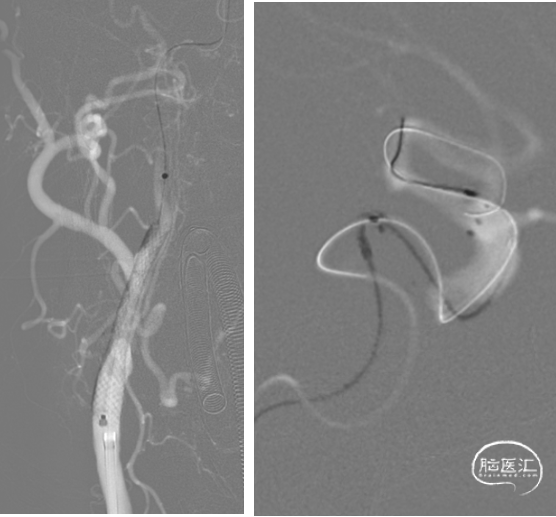

术中过程:逐段球囊扩张

术中过程:释放支架过程